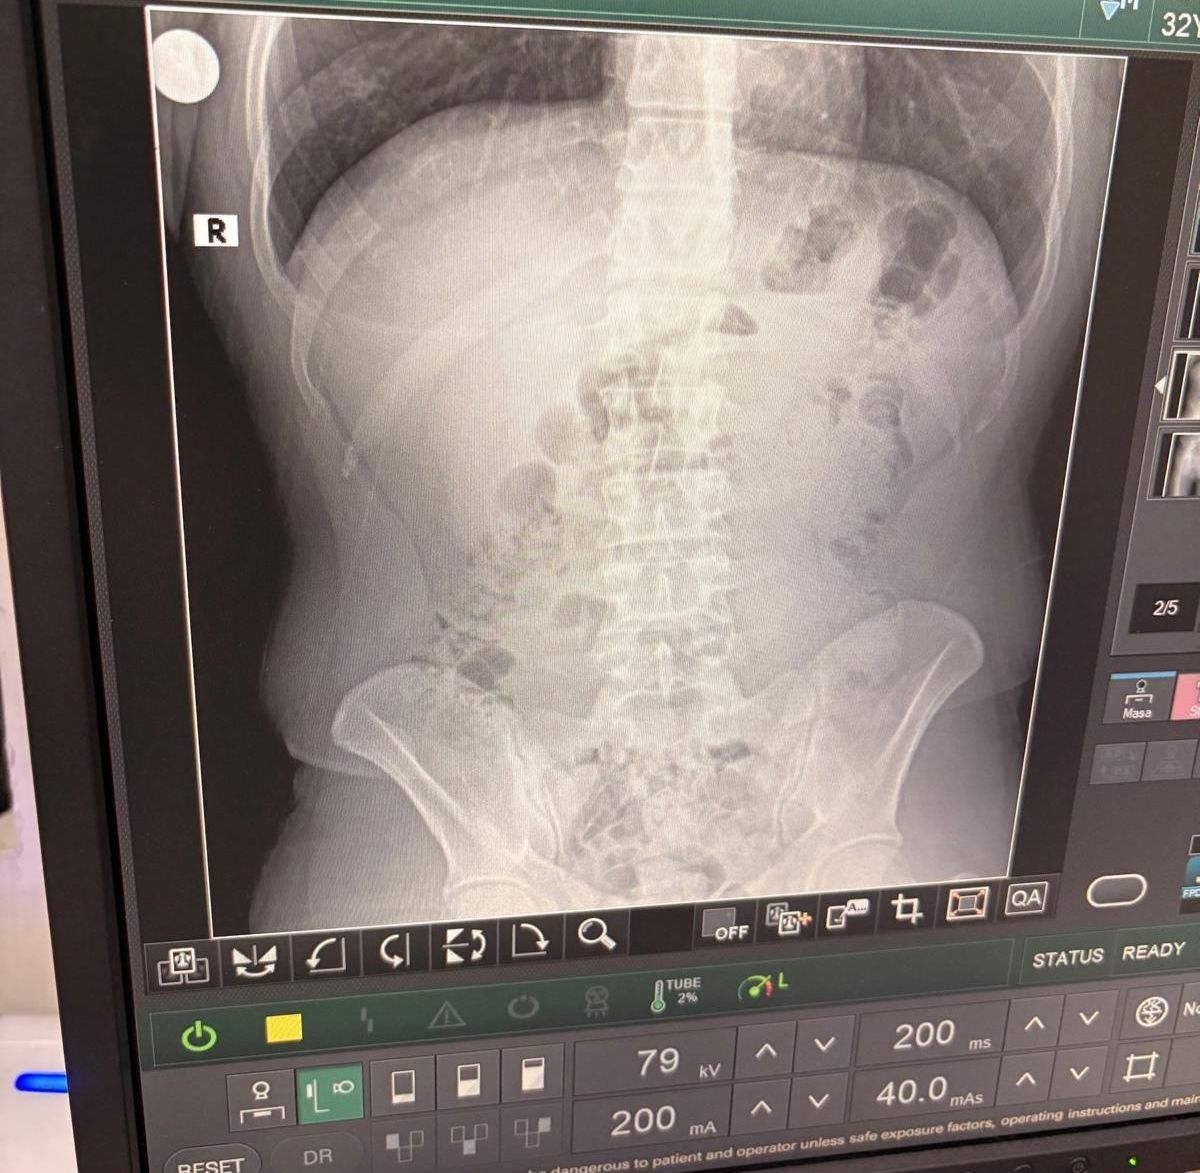

Röntgen Filmleri Gerçeği Ortaya Çıkardı

Şüphelilerin mide ve bağırsaklarında çok sayıda kapsül tespit edildi. Hastanede yapılan tıbbi müdahaleler sonucunda, toplam 140 kapsül içinde 1 kilo 516 gram metamfetamin ele geçirildi.